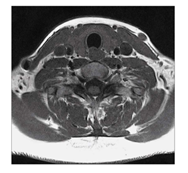

MRI lehetővé teszi, hogy megjelenítsék morfológiai változások: a csigolyatestek, porckorongok, gerincvelő, dura térben, az ideg gyökerek környező paravertebralis lágyrész, érrendszeri szerkezetek, amelyek a kutatási területen.

T1VI T2VI (keverjük) T2VI

Meningeoma felső nyaki régióban a gerinccsatorna

T2VI T1 (kontraszt)

Ependimoma a gerincvelő. MR minta degeneratív változások a nyaki gerinc, a C5-C6 lemez extrudálás, C6-C7, C7-Th1.

T2VI T1 (kontraszt)